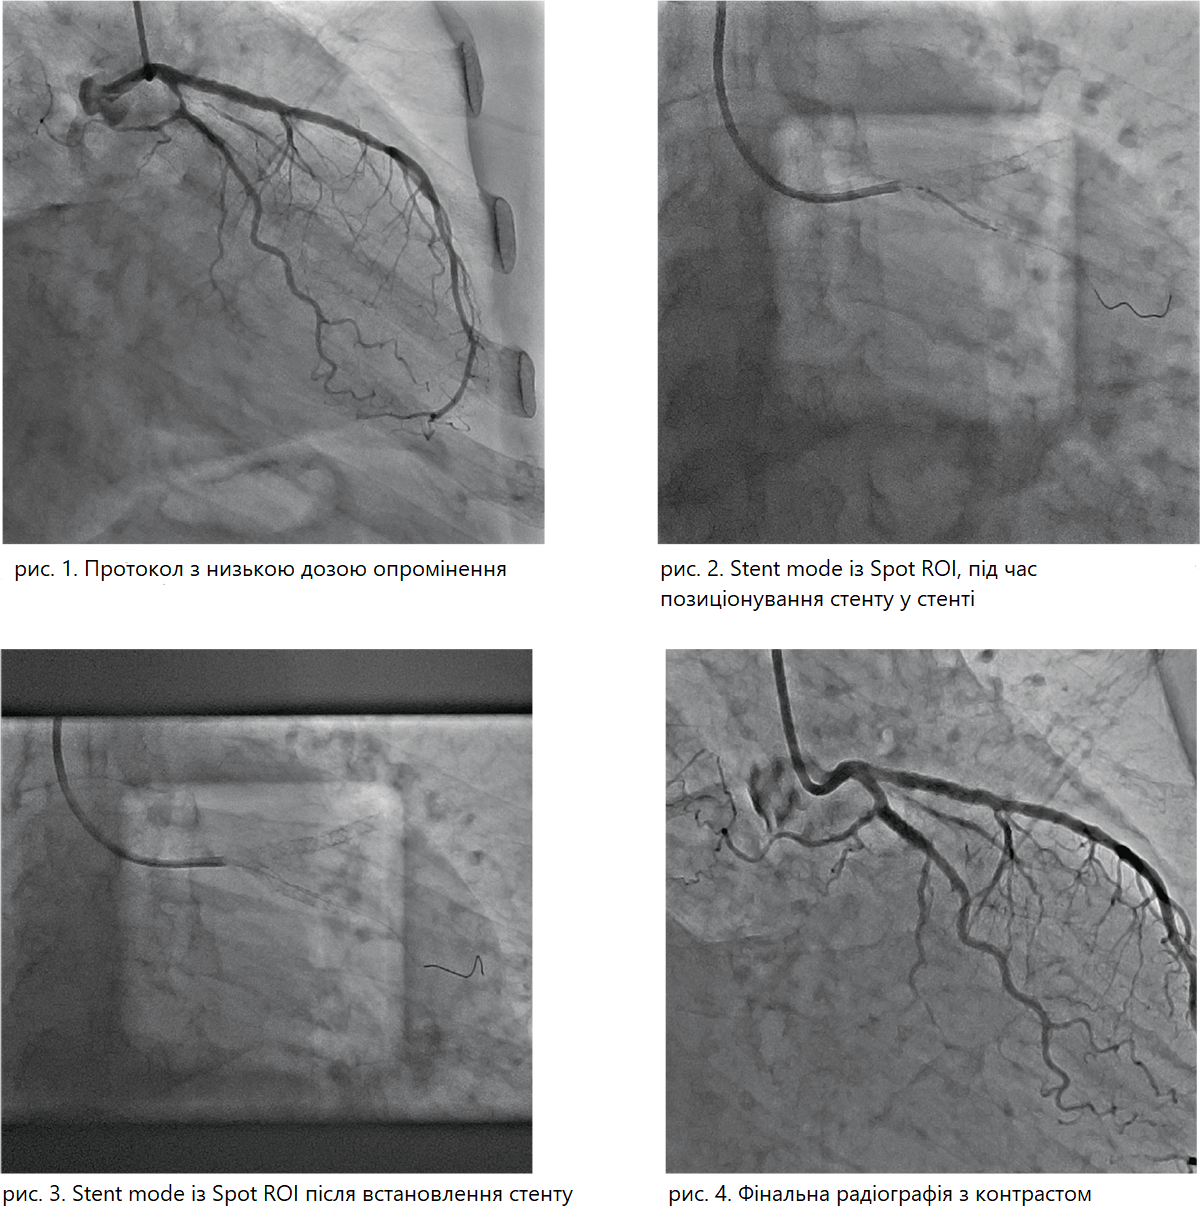

З моменту відкриття нової операційної, Alphenix Core + перевершив усі очікування. По-перше, вони побачили неймовірну якість зображення завдяки технології обробки зображень Illuvis від Canon Medical, яка при збереженні якості зображення, дозволяє зменшити кількість кадрів із 15 до 10 на секунду. Їм також вдалося зменшити дозу до 85% завдяки технології Spot ROI.

По-друге, під час виконання інтервенційних процедур зі стентами, новий протокол Alphenix Stent Mode забезпечує додаткове покращення візуалізації стентів, а також забезпечує візуалізацію в реальному часі без будь-яких артефактів від маркерів балону.